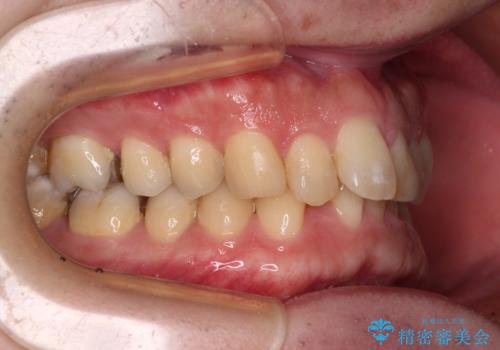

- 深い咬み合わせによる食いしばりで、顎関節や頭が痛むことがあるとのことで来院された患者様です。

歯ぎしりができないくらい強い食いしばりの咬合状態であったため、奥歯の歯軸を起き上がらせることで咬合を挙上させ、歯ぎしりができるようにしていくこととしました。

下顎が左側にずれているため、上下正中は最大限合わせられるところまで合わせるゴールとなりました。